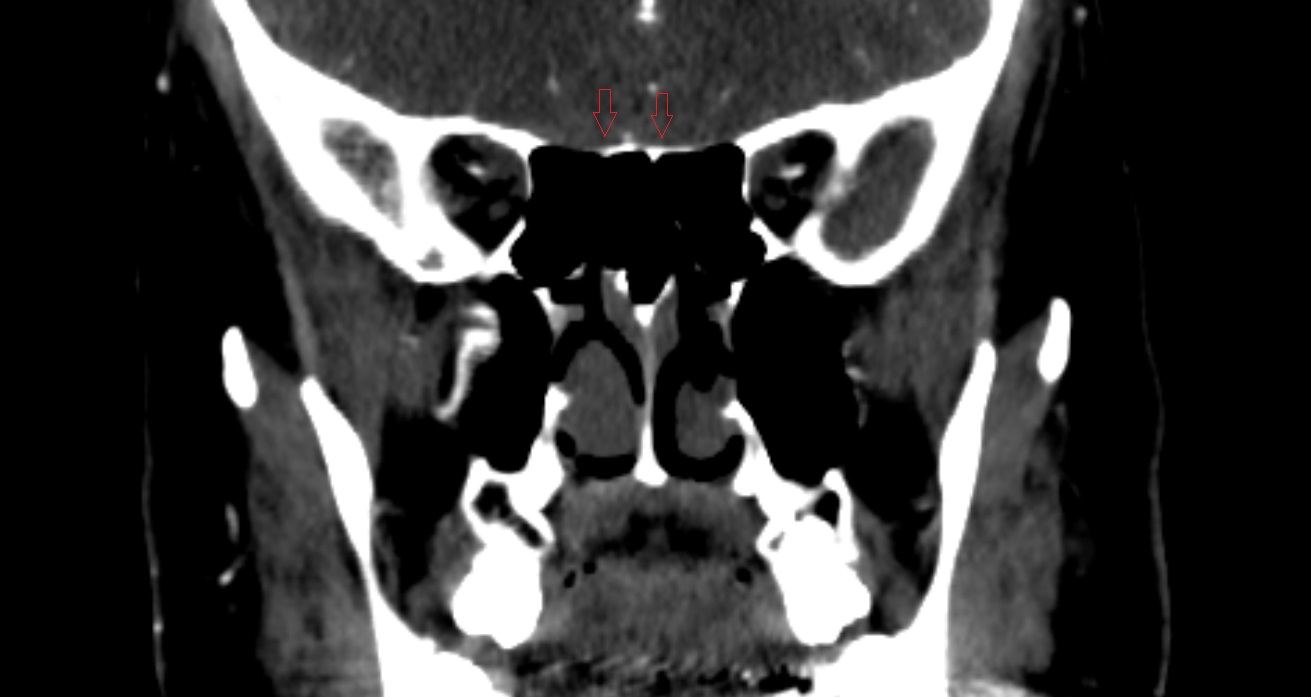

- Optic chiasm